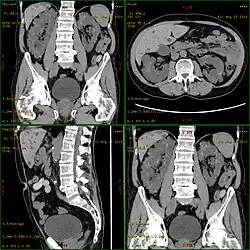

Die Diagnose wird in der Regel durch eine Sonografie („Ultraschall“)[14] oder durch andere bildgebende Verfahren, wie beispielsweise die Magnetresonanztomografie, gestellt.[15] Mit der Sonografie können mit modernen Geräten Zysten bis herab zu einer Größe von 5 mm diagnostiziert werden. Die Früherkennungsrate bei 20-jährigen Patienten liegt bei etwa 90 %.[16] Die Computertomografie bietet zwar eine höhere Auflösung mit besserer Bildqualität, sie wird jedoch vor allem wegen der Strahlenbelastung nicht für Patienten-Screenings, sondern nur bei speziellen diagnostischen Fragestellungen eingesetzt.[3]

Die Entstehung und Entwicklung von Zystennieren, die Pathogenese, beruht auf einer zystischen Degeneration der sogenannten Nierenkanälchen (Tubuli, auch: Harnkanälchen) in den Nieren. Diese führt bei der autosomal-dominant vererbten PKD im Verlauf von Jahrzehnten zu einer zunehmenden Vergrößerung der Nieren. Es kann dabei zu einer Funktionseinschränkung bis hin zum völligen Verlust der filtrativen Nierenfunktion kommen. Beide Nieren sind gleichmäßig betroffen. Mehrere hundert Zysten, die in ihrer Erscheinung prall elastisch sind, können dabei pro Organ ausgebildet werden. Masse und Volumen der Nieren können dadurch erheblich anwachsen. Während eine gesunde Niere durchschnittlich eine Masse von 160 g aufweist, können polyzystische Nieren bis zu 8 kg bei bis zu 40×25×20 cm³ (= 20 Liter) Volumen erreichen (gesunde Niere: 12×6×3 cm³ = 0,216 Liter). Trotz des erheblich gesteigerten Platzbedarfs des Organs kommt es nur relativ selten zu Funktionsstörungen der benachbarten Organe.[24]

Das Durchschnittsalter bei Diagnosestellung der ADPKD liegt derzeit bei 27 Jahren. Wenn eine Nierenfunktionseinschränkung eintritt, kommt es zu einer raschen Abnahme der GFR von ≈5,9 ml/min pro Jahr. Bislang war keine randomisierte Studie in diesem späten Stadium der Erkrankung in der Lage, den günstigen Effekt einer Behandlung nachzuweisen. Wegen der langen präsymptomatischen Phase und des späten Auftretens der Niereninsuffizienz sind die primären Endpunkte, welche üblicherweise bei Studien zu chronischen Nierenerkrankungen untersucht werden, wie Zeit bis zur Dialysebehandlung, Verdoppelung des Serum-Kreatinins oder Tod, bei Studien zu polyzystischen Nierenerkrankungen nur bedingt brauchbar.[94] Aus diesem Grund wurde das Consortium for Radiologic Imaging Studies of Polycystic Kidney Disease. (CRISP) gegründet, dessen Aufgabe es ist, bildgebende Verfahren zu untersuchen, die in den Frühstadien Aussagen zum Erkrankungsverlauf ermöglichen. Ein wichtiges Ergebnis der Untersuchungen von CRISP mittels Magnetresonanztomographie ist, dass bei Patienten mit ACPKD die Zysten kontinuierlich und quantifizierbar wachsen und dass das Zystenwachstum mit der Abnahme der Nierenfunktion korreliert. Das heißt, eine stärkere Zunahme der Zystengröße ist mit einer schnelleren Abnahme der Nierenfunktion assoziiert.[95]